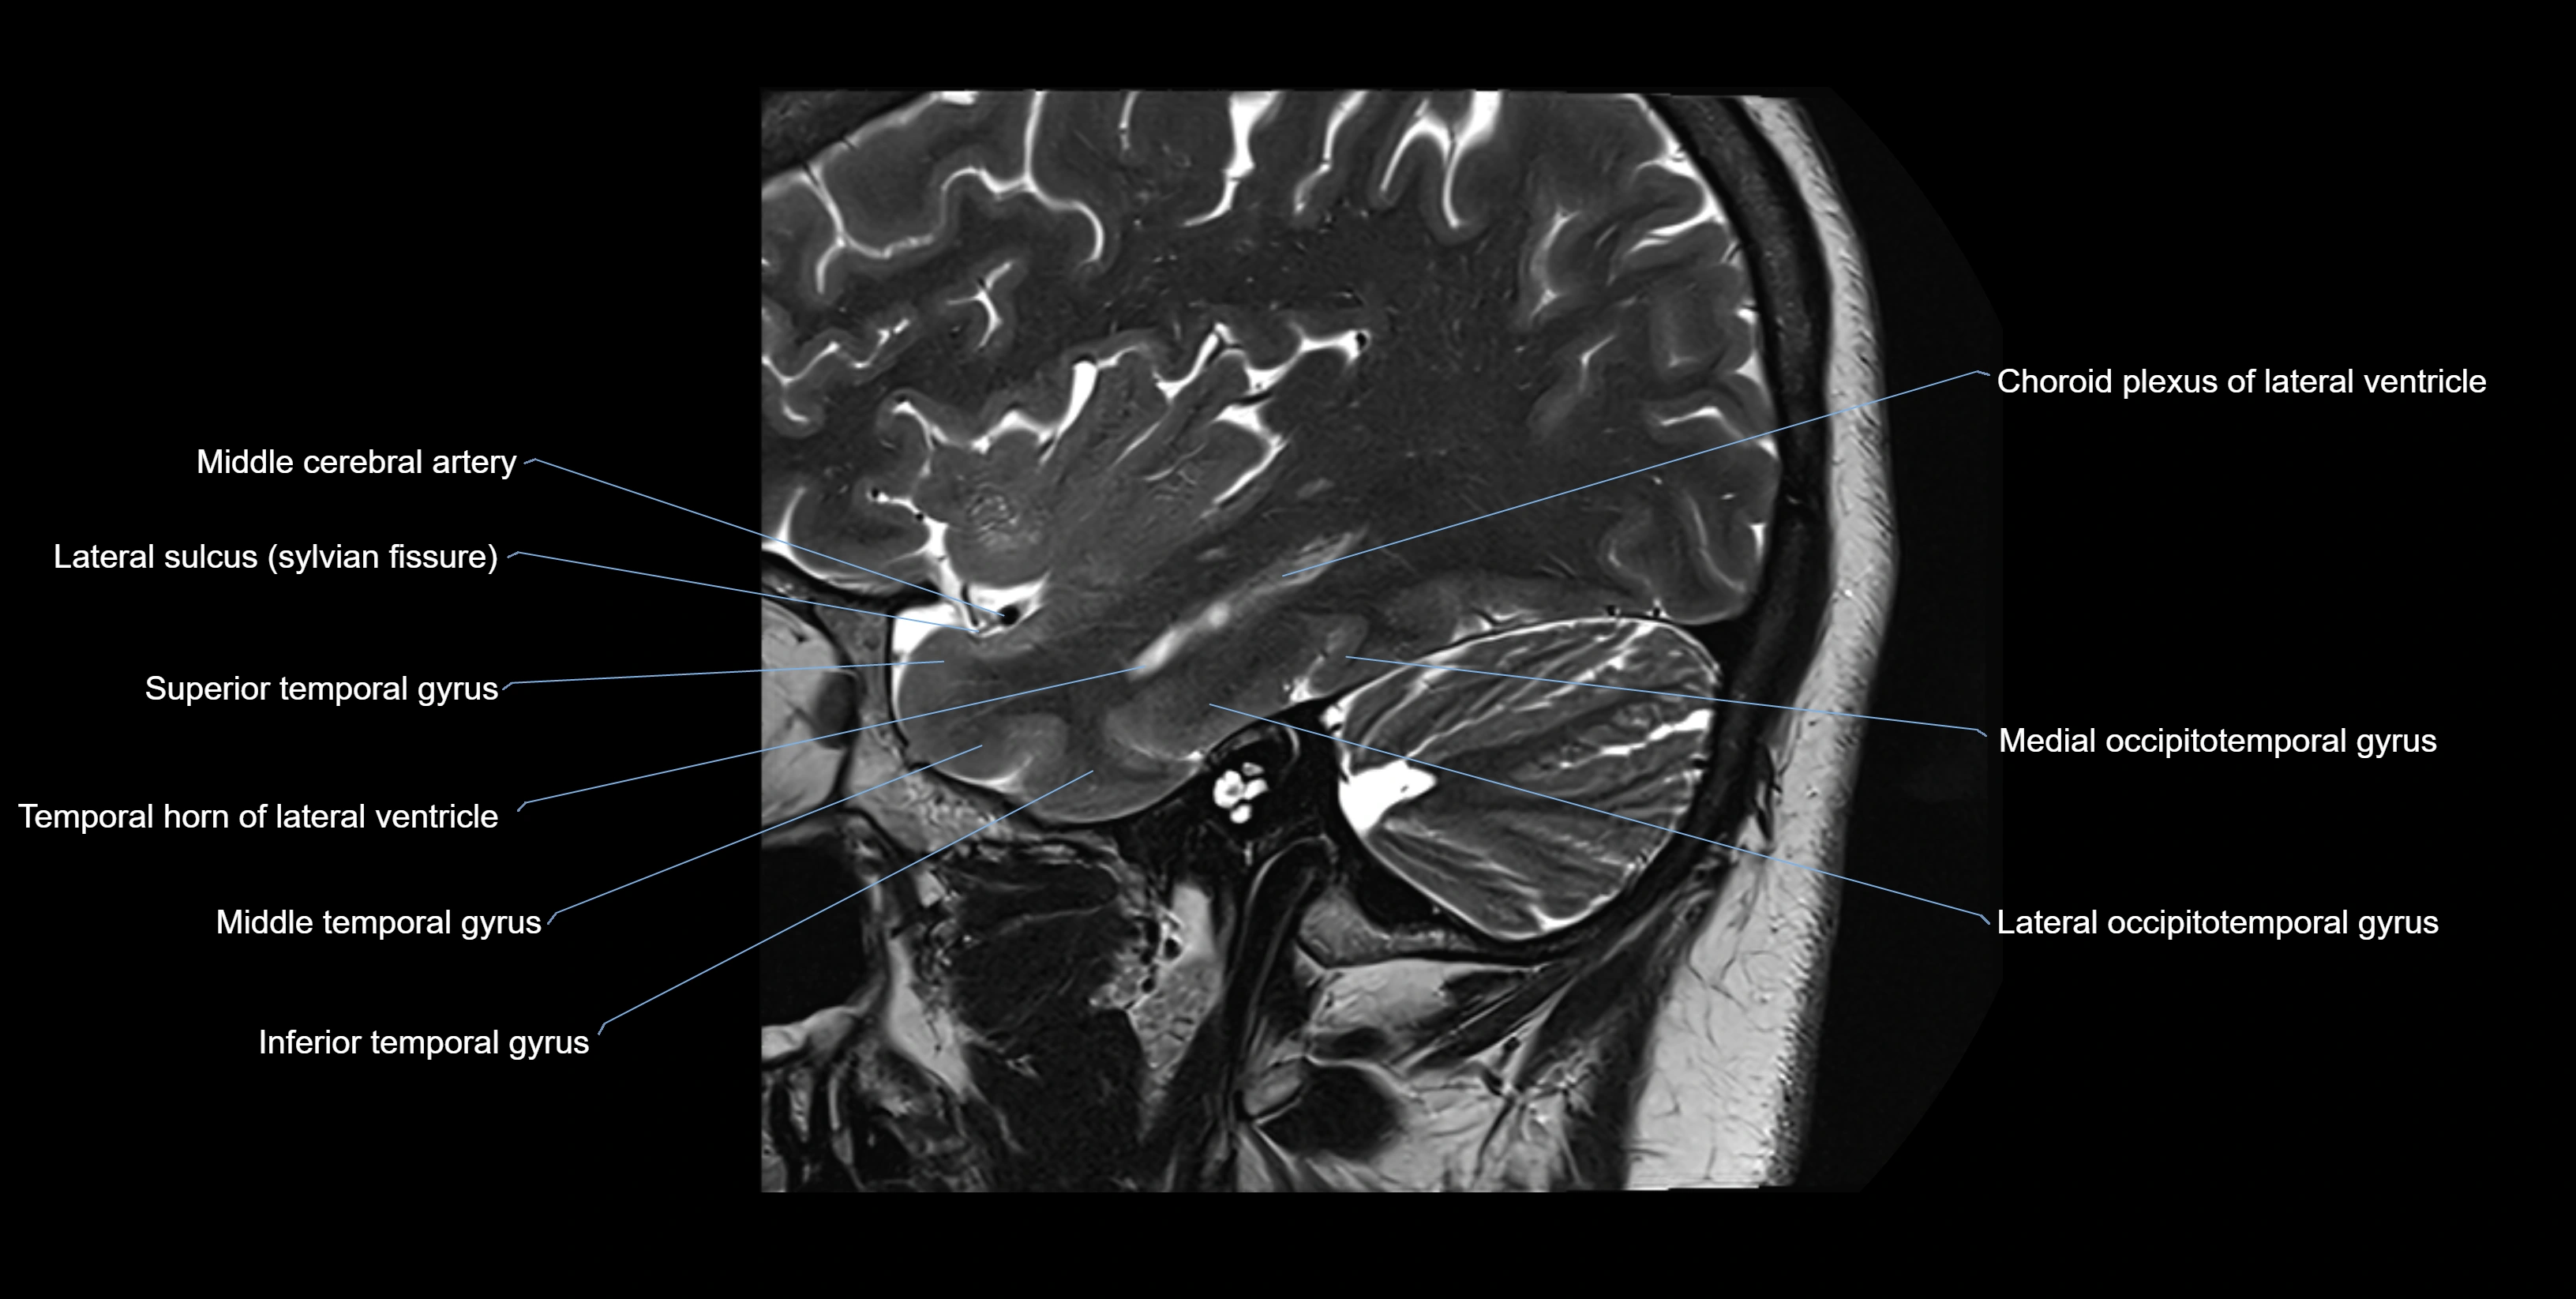

Location and Structure

• Position: Lies on the ventricular (superior) surface of the hippocampus, beneath the ependyma of the inferior horn of the lateral ventricle.

• Superiorly: Ependyma and CSF of the temporal horn of the lateral ventricle

• Inferiorly: Pyramidal cell layer of the hippocampus (CA1 region)

• Medially: Fimbria and fornix

• Laterally: Temporal lobe white matter and parahippocampal gyrus